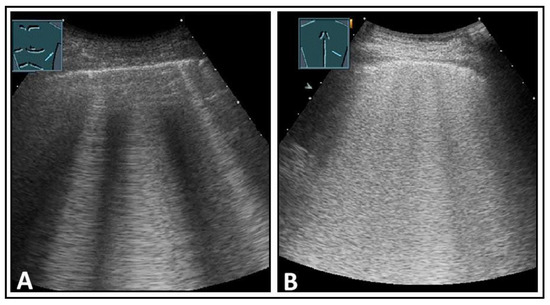

7. Other Pathologic Situations